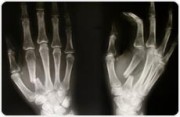

Die Praxisklinik bietet das komplette Spektrum der Handchirurgie einschließlich Mikrochirurgie der Nerven und Gefäße an den oberen und unteren Extremitäten an.

Bei akuten Erkrankungen handelt es sich meistens um Unfallverletzungen - Frakturen, die operativ mit Schrauben, Drähten oder Platten versorgt werden müssen. Des Weiteren auch Bandverletzungen der Gelenke oder Verletzungen der Nerven und Gefäße.

Eine häufige Erkrankung des Gewebes an der Handinnenfläche. Es kommt zu Strangbildungen, die bis zu den Fingern reichen und dann über Jahre die Finger allmählich verkrümmen. Durch eine frühzeitige operative Behandlung werden die Verhärtungen in der Hand entfernt und die Streckfähigkeit der Finger wieder hergestellt.